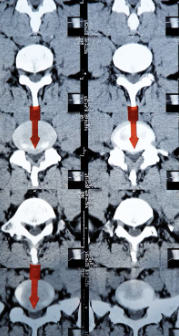

허리디스크는 디스크가 터져서 신경을 누를 경우 생기는 것으로 보통 4,5번에서 많이 발생하고 디스크가 터진 양이 적다면 터진 순간부터 수분이 날아가면서 양이 많이 없어지는데 그렇지 않고 양이 많을 경우 극심한 통증이 생깁니다.

허리디스크를 정확하게 진단하기 위해서는 엑스레이로는 힘들며, MRI를 통해 검사해야 정확하게 볼 수 있습니다.

MRI가 몸에 좋지 않지만 허리 통증으로 엑스레이만 진행 할 경우 오진이 많아 지속적인 통증이 계속 된다면 허리디스크를 의심하고 MRI 검사를 한번 받아보시길 권유드립니다.